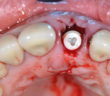

POINT DE CONTACT INTERPROXIMAL EN ZONE ESTHÉTIQUE POINT DE CONTACT INTERPROXIMAL ET ESTHÉTIQUE GINGIVALE EN SECTEUR ANTÉRIEUR L’esthétique gingivale en…